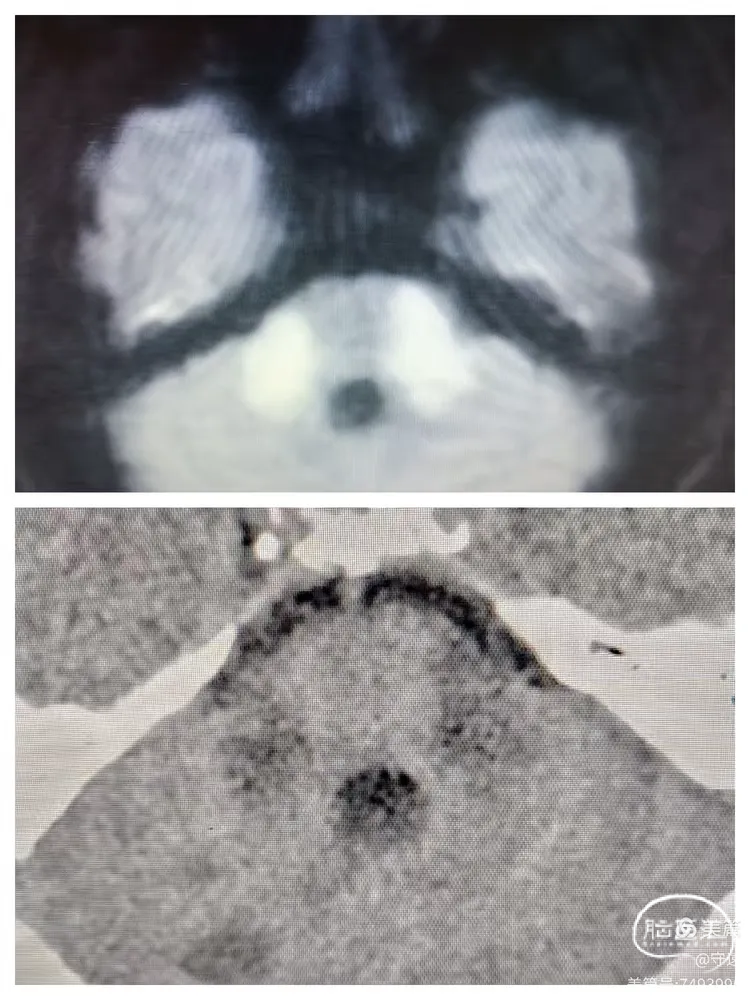

患者可按指令动作,言语障碍,左侧下肢力弱,生命体征正常。复查CT:双侧桥臂浅淡低密度影,与术前核磁大致相同,无出血征像。中脑、延髓区域未见明显梗塞。

术前核磁与术后12小时CT检查对照

2.双侧大脑脚梗死影像学犹如米老鼠两只耳朵,称之为“米老鼠耳征."